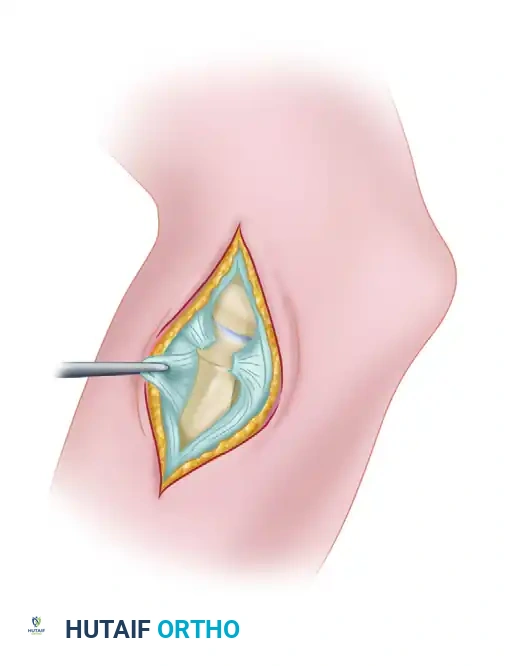

Figure: Dislocation of the radial head demonstrating a ruptured annular ligament. In acute settings, this ligament can often be sutured satisfactorily.

Step 3: Ligament Repair or Reconstruction

* Primary Repair: If the tissue quality is robust, the annular ligament is repaired directly to its ulnar footprint using suture anchors or transosseous sutures.